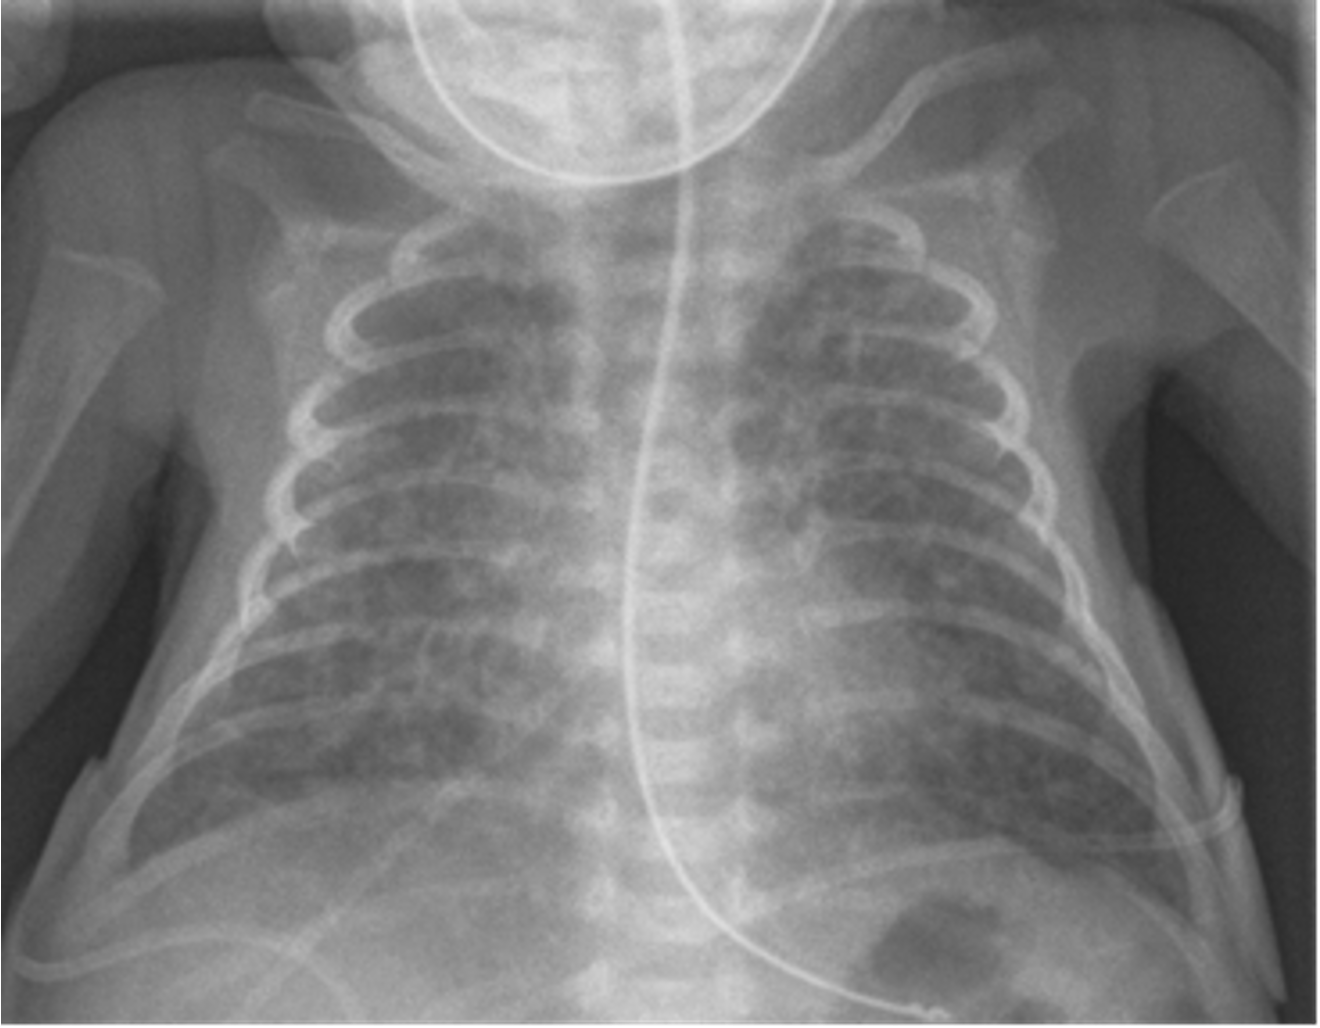

Xray findings

- Prominent perihilar streaking reflecting fluid in the interstitium

- Patchy infiltrates

- Fluids in the horizontal fissure on fifth right costal

- Hyperinflated lung

- Chest X-ray Findings: